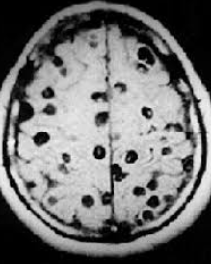

Adult onset seizure in an immigrant from Argentina (5 years ago). No PMH. PE normal. CBC and CMP WNL. MRI shown below:

Neuroimagin reveals a scolex

Neurocystercosis: pork tapeworm (Taenia solium) which is endemic to developing countries. Presents with adult onset seizure and evidence of at least one or more cystsin the brain parenchyma. Tx with corticosteroids and albendazole.

Can look like this